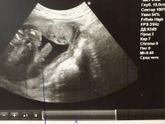

Проснулась сегодня с мыслью, что нужно подстричься . Волосы уже были ниже плеч, решила опять вернуться к каре. Я не особо люблю кудри, но бонусом сделали укладку. Настроение весеннее. 25 неделька, вещички прикупаем.